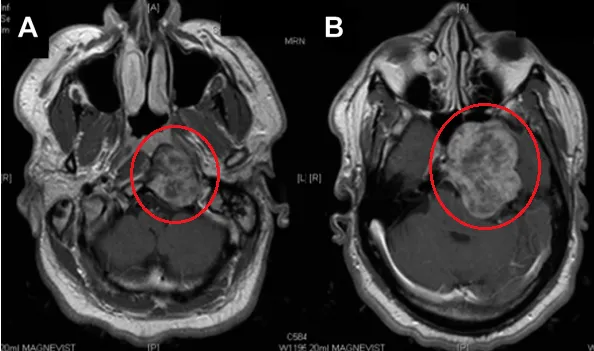

MR检查:颞下和斜坡区域巨大肿瘤(脊索瘤可能),存在广泛的岩骨和斜坡骨质侵蚀,肿瘤并向海绵窦侵袭(图A-B)。

图A&B:增强磁共振T1加权像显示颞下窝较大占位,肿瘤延伸至舌下神经管(HC)水平的咽后间隙。肿瘤向前侵犯蝶窦,并向后颅窝和中颅窝浸润,无硬膜内浸润。